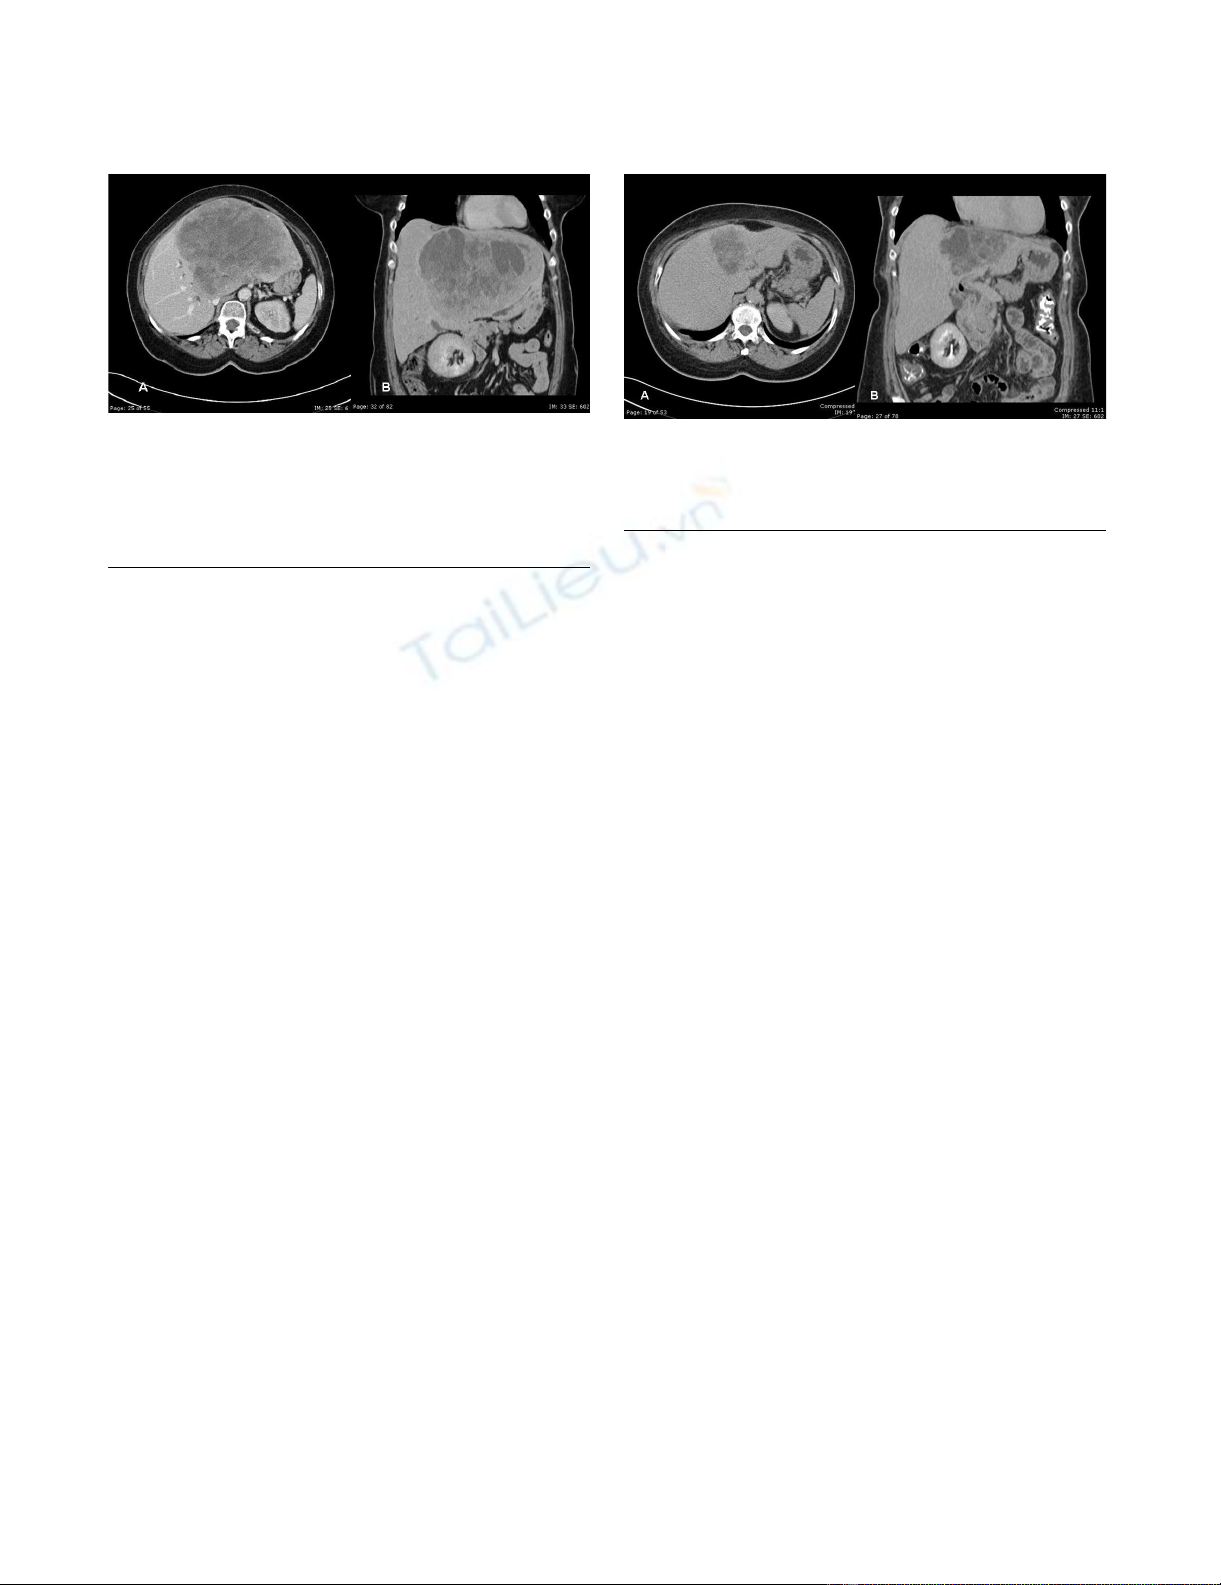

Case presentation

A 67-year-old woman presented with epigastric fullness,

mild jaundice and a 12-pound weight loss over a period

of 3 months. The patient had a history of a bowel resec-

tion 7 years prior to presentation for an unknown malig-

nancy. On physical examination, her abdomen was soft

with a palpable and non-tender mass in the mid-epigas-

trium. Initial work-up including ultrasonography revealed

a large liver lesion, follow-up CT confirmed the presence

of a heterogeneous mass 17.5 cm in diameter replacing

most of the left lobe of the liver (Figure 1a, 1b) with

marked compression of the right biliary tree. Initial Liver

function testes showed:

Computerized tomography A) and B); evaluation of the liver demonstrated a large inhomogeneous mass with multiple areas of cystic component within the left lobe of the liverFigure 1

Computerized tomography A) and B); evaluation of the liver

demonstrated a large inhomogeneous mass with multiple

areas of cystic component within the left lobe of the liver.

The mass measured 17.6 × 14 cm. Mild dilatation of the int-

rahepatic biliary radicals in the right lobe liver.